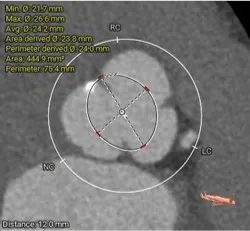

瓣上多平面分析

• 三叶式主动脉瓣,以风湿性改变为主,瓣叶显著增厚,R-L间纤维粘连,轻度钙化,钙化主要沿无冠窦瓣缘分布,LVOT直筒型对人工瓣膜的释放技巧有较高要求

• 左、右冠高度可,切线位测量,无冗长瓣叶,结合瓦氏窦、STJ 内径综合预估,冠脉阻塞风险适中

• 结合瓣环及瓣上分析数据,选择18mm球囊预扩,尽可能减小破坏瓣上结构,植入TaurusElite系统AV26瓣膜,视评估情况决定是否后扩。